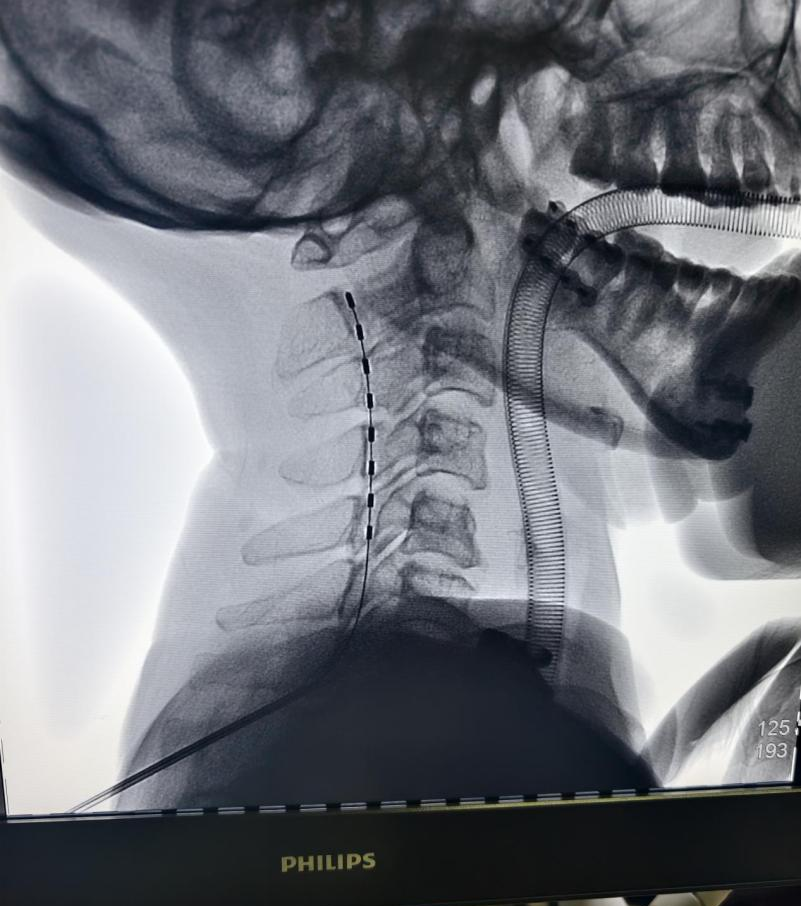

“脊髓电刺激就像在神经传导通路上安装一个‘起搏器’,”神经内科副主任张小刚解释道,“通过植入颈段脊髓的电极发放微弱电流,可以上行激活大脑皮层网络,促进神经网络重组与功能连接,从而为促醒创造生理基础。”

这是一个需要勇气的决定,更是一个需要精密协作的系统工程。与家属进行充分沟通并获得同意后,2026年1月16日,由神经外科功能神经亚专业组主任医师杜寒剑、冯怡墨,副主任医师赵泽楠,博士邵川组成的手术团队,凭借精湛的技术,成功为李女士植入了脊髓电刺激器(临时)电极。手术过程顺利,次日即开机进行调控治疗。